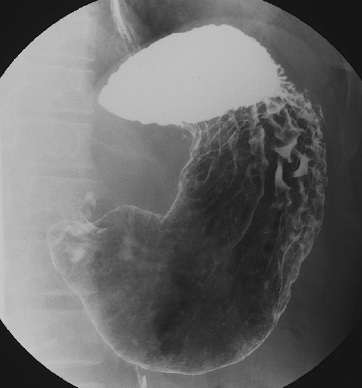

X線透視検査

「体内の臓器の状態をエックス線で観察」

エックス線透視検査とは、バリウムと呼ばれる造影剤を使用した胃や大腸の検査のほか、手術後の透視、骨折や脱臼の整復、エックス線で透視した画像を見ながら内視鏡を用いて行うERCP(内視鏡的逆行性胆管膵管造影)、気管支鏡で組織を採取するTBLB(経気管支肺生検)などがあります。

検査時間

- 胃…約20分

胃の透視検査